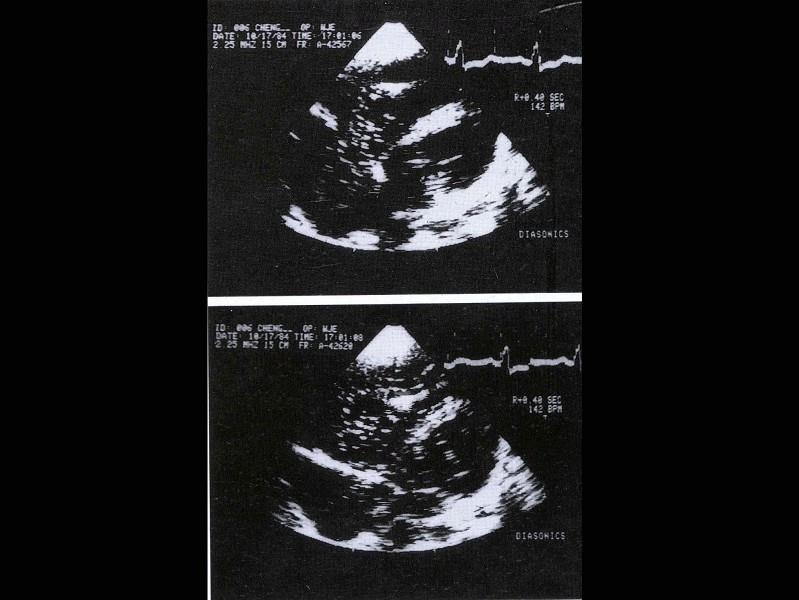

选项 A.生理盐水 B.葡萄糖溶液 C.双氧水 D.声振微气泡造影剂 E.一氧化碳气体

答案 D